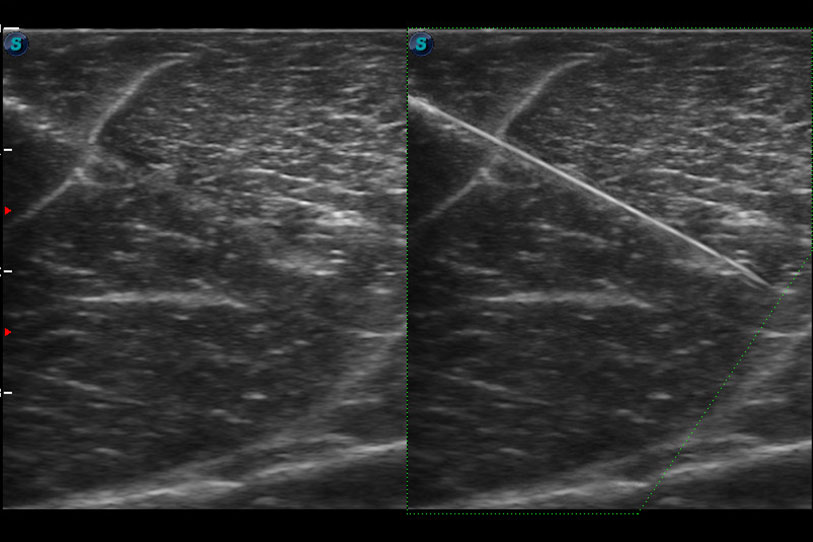

增強(qiáng)穿刺針在動(dòng)物解剖結(jié)構(gòu)中的位置,提高穿刺介入的安全性和準(zhǔn)確性。